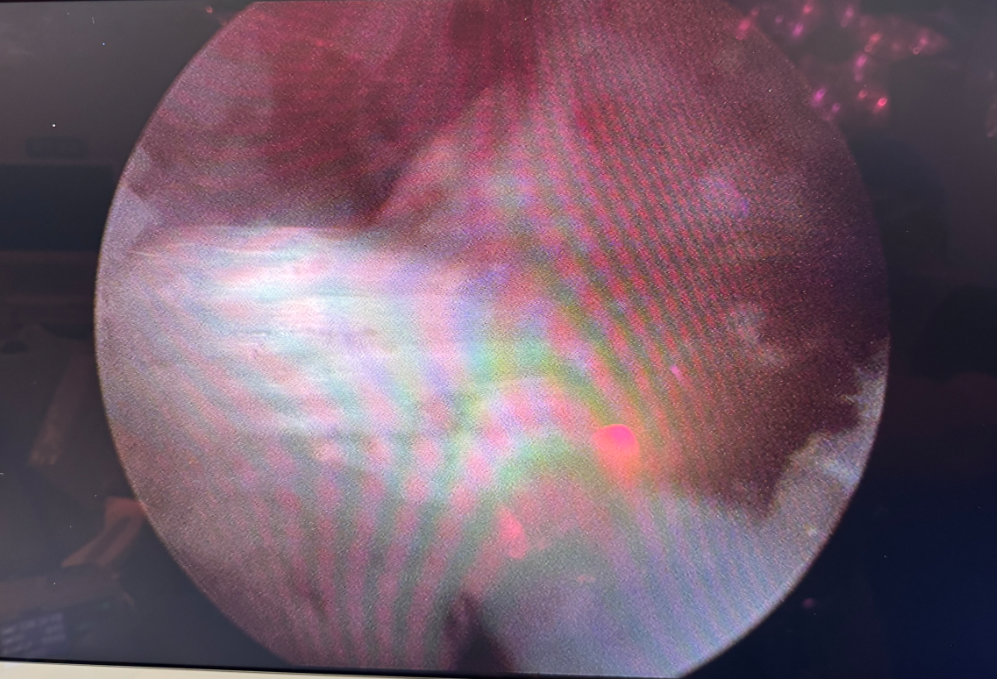

▲术后镜下影像(人工韧带走向良好)